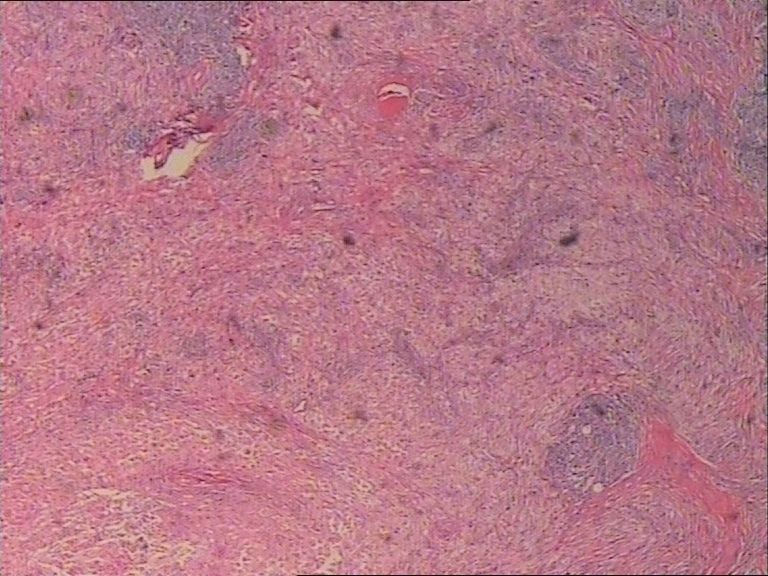

表皮下肿块FNAC一例,体现了该诊断手段的优势。

患者 女 47岁 腰部皮下肿块5x4cm,皮肤表面灰褐色,无隆起,无压痛。体格检查无其他异常。

诊断是Rosai-Dorfman病。

是的,单核及多核组织细胞是本病不特异但恒定的特点。

涂片内见较多组织细胞和多核巨细胞。肉芽肿性炎。